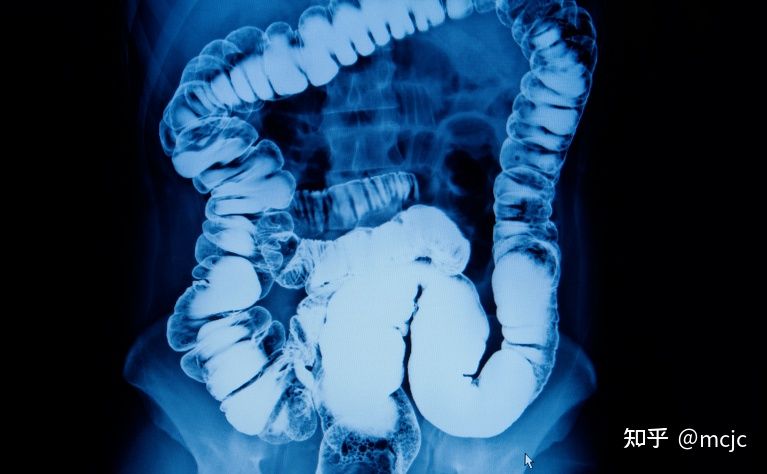

哎呀,说到克罗恩病在X光上的表现,真是个让人头疼的话题。想象一下,那些可怜的X光片上,肠道就像是经历了一场狂风暴雨,扭曲得不成样子。这些影像,不仅仅是黑白斑驳,更是医生和患者心中的一块大石头。

你看那些肠道,原本应该是平滑流畅的,现在却像被什么东西啃咬过一样,坑坑洼洼的。有时候还能看到肠道壁增厚,像是穿上了一层厚厚的棉衣,这可不是什么好兆头。更糟糕的是,肠道的某些部分还会出现狭窄,就像是一条原本宽阔的河流,突然间变成了小溪流,水流不畅,淤积成灾。

这些X光片,不仅仅是医学图片,它们是疾病的见证,是患者痛苦的写照。每一次看到这样的影像,我的心都揪得紧紧的,感觉就像是自己的身体也跟着不舒服一样。克罗恩病,这个顽固的家伙,真是让人又恨又无奈。